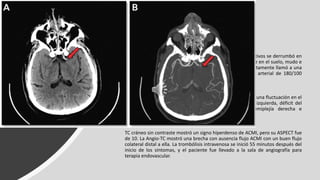

• Masculino de 62 años sin antecedentes médicos significativos se derrumbó en

su baño. El ruido alertó a su hijo, que encontró a su padre en el suelo, mudo e

incapaz de mover el lado derecho de su cuerpo. Inmediatamente llamó a una

ambulancia. Los paramédicos cuantificaron una presión arterial de 180/100

mm Hg y un pulso irregular.

En el departamento de emergencias, el paciente presentaba una fluctuación en el

estado de alerta, desviación forzada de la mirada hacia la izquierda, déficit del

campo visual derecho, afasia global con mutismo, hemiplejía derecha e

hipoestesia derecha severa. Su puntaje NIHSS fue de 22.

TC cráneo sin contraste mostró un signo hiperdenso de ACMI, pero su ASPECT fue

de 10. La Angio-TC mostró una brecha con ausencia flujo ACMI con un buen flujo

colateral distal a ella. La trombólisis intravenosa se inició 55 minutos después del

inicio de los síntomas, y el paciente fue llevado a la sala de angiografía para

terapia endovascular.

La punción en la ingle tuvo lugar 67 minutos después del inicio de los síntomas. La

inyección inicial de contraste en la ACI izquierda mostró que este vaso estaba ocluido en la

parte superior de su segmento supraclinoideo.

Con trombectomía mecánica y stent hubo recanalización completa con reperfusión

completa. El paciente comenzó a mejorar en la mesa angiográfica y continuó mejorando

durante la noche. A la mañana siguiente, su puntaje NIHSS fue 3. La TC repetida mostró un

infarto pequeño en el núcleo lenticular izquierdo.

A los 3 meses, el paciente tenía una función completa y sin síntomas residuales.